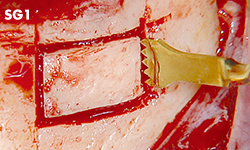

Unilateral anterior mandibular sampling

Excision of bone torus

Anterior mandibylar harvesting

Mandibular harvesting at approach stage

The cutting part is bone torus